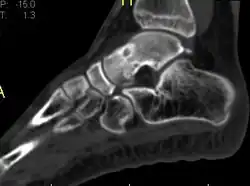

Radiographs in osteoid osteoma typically show a round lucency, containing a dense sclerotic central nidus (the characteristic lesion in this kind of tumor) surrounded by sclerotic bone. The nidus is seldom larger than 1.5 cm.

The lesion can in most cases be detected on CT scan, bone scans and angiograms. Plain radiographs are not always diagnostic. MRI adds little to the CT findings which are useful for localisation. Radionuclide scanning shows intense uptake which is useful for localisation at surgery using a hand held detector, and for confirmation that the entire lesion has been removed.[8][9]

1 a. Osteoid osteoma (front view) showing cortical thickening mid-tibia -

1 b. Osteoid osteoma (side view): clearly seen by high resolution CT with a small well-defined lucent nidus in the mid tibial shaft. -

2. CT scan showing an osteoid osteoma of the fibula with a clearly visible nidus -

Nidus demonstrated by high resolution CT